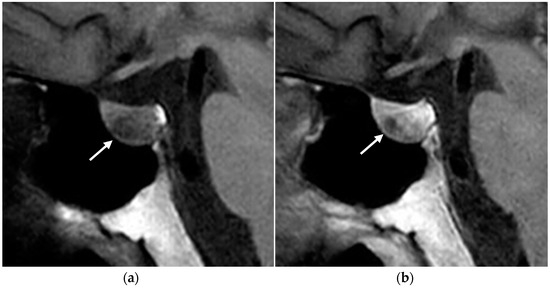

MRI

- Gotway, M.B.; Reddy, G.P.; Webb, W.R.; Morita, E.T.; Clark, O.H.; Higgins, C.B. Comparison between MR Imaging and99m Tc MIBI Scintigraphy in the Evaluation of Recurrent or Persistent Hyperparathyroidism. Radiology 2001, 218, 783–790. [Google Scholar] [CrossRef]

- Scheepers, M.H.M.C.; Al-Difaie, Z.; Brandts, L.; Peeters, A.; Winkens, B.; Al-Taher, M.; Engelen, S.M.E.; Lubbers, T.; Havekes, B.; Bouvy, N.D.; et al. Diagnostic Performance of Magnetic Resonance Imaging for Parathyroid Localization of Primary Hyperparathyroidism: A Systematic Review. Diagnostics 2023, 14, 25. [Google Scholar] [CrossRef]